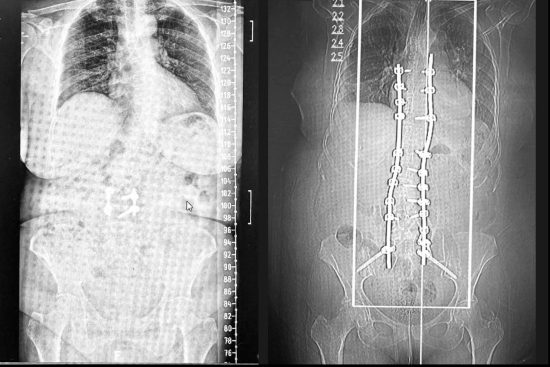

La escoliosis degenerativa del adulto es una afección que afecta a un número creciente de personas mayores, provocando dolor crónico y limitaciones funcionales. Gracias a los avances tecnológicos, el tratamiento quirúrgico de esta condición ha experimentado una transformación significativa. El Dr. Carlos Botella-Asunción, neurocirujano con más de 35 años de experiencia, nos explica cómo la implementación de guías 3D personalizadas ha mejorado la precisión y seguridad de estas intervenciones

La tecnología de guías 3D permite diseñar dispositivos personalizados que se ajustan a la anatomía única de cada paciente. A partir de estudios de imagen como radiografías, tomografías computarizadas y resonancias magnéticas, se crea un modelo tridimensional de la columna. Este modelo se utiliza para planificar la cirugía y fabricar guías que facilitan la colocación precisa de tornillos pediculares y otros dispositivos de fijación durante la intervención.

Las guías 3D proporcionan una precisión máxima en la colocación de implantes, reduciendo el riesgo de errores y complicaciones. Además, al optimizar la planificación quirúrgica, se disminuye el tiempo de la intervención, la exposición a RX y se favorece una recuperación más rápida del paciente. La seguridad también se incrementa, ya que se minimiza el riesgo de dañar estructuras cercanas como raíces nerviosas o vasos sanguíneos.